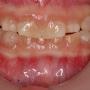

Anterior view of the dentition before treatment